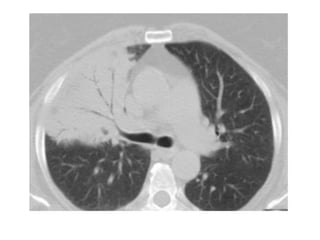

A, Unenhanced axial high-resolution CT through left mid (A) and lower (B) lung

show peripheral honeycombing, which is greatest in lower lobe,

accompanied by traction bronchiectasis and scattered peripheral reticular

opacities. Honeycombing is most prominent feature in this patient, typical for

idiopathic pulmonary fibrosis